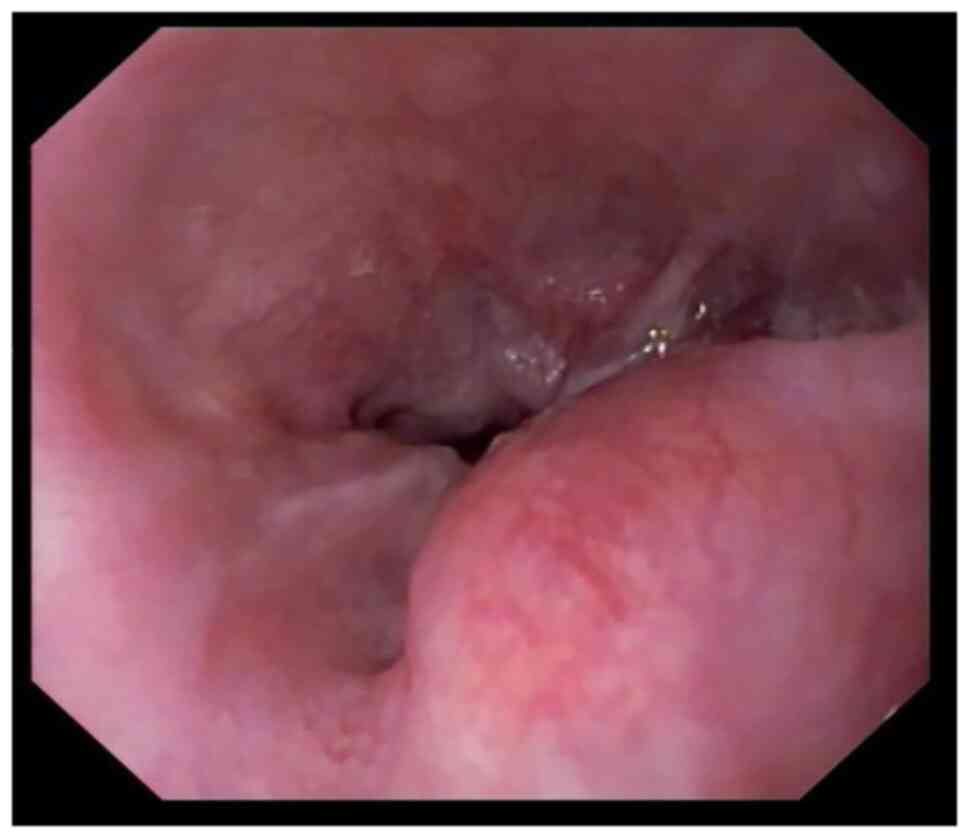

Fusion of the anaplastic lymphoma kinase (ALK) gene is a rare driver in non‑small cell lung cancer (NSCLC). Lorlatinib is a third‑generation ALK inhibitor approved for the treatment of locally advanced or metastatic ALK+ NSCLC. The traditional administration method of lorlatinib is whole tablet ingestion, while the efficacy effect of gastric tube injection after water dissolution remains unclear. In the present report, a marked response to lorlatinib in a 49‑year‑old patient with ALK+ NSCLC who was administered lorlatinib through a gastric tube, was described. The patient had received chemotherapy combined with immune checkpoint inhibitors prior to targeted drug therapy and developed hyperprogression, which was mainly manifested as rapid enlargement of the primary lesion with multiple new systemic metastases, accompanied by poor performance status score, esophageal compression and difficulty eating. The patient was injected with pre‑dissolved lorlatinib through the nasogastric tube. After 6 days, related symptoms, such as dyspnea and dysphagia, were relieved. After 18 days, the esophageal stenosis was significantly alleviated, and the gastric tube was removed. In conclusion, gastric tube injection be used as a means of lorlatinib administration in patients with ALK+ NSCLC with dysphagia, regardless of previous immunotherapy‑associated hyperprogression.

Longo V, Catino A, Montrone M, Pizzutilo P, Ugenti I, Lacalamita R, Del Bene G, Pesola F, Marech I and Galetta D: Esophageal stricture caused by ALK-positive NSCLC esophageal metastasis resolved after a few days of lorlatinib therapy without stent placement. JTO Clin Res Rep. 1:1000442020.PubMed/NCBI

Sasaki K, Yokota Y, Isojima T, Fujii M, Hasui K, Chen Y, Saito K, Takahata T, Kindaichi S and Sato A: Enteral lorlatinib after alectinib as a treatment option in anaplastic lymphoma kinase-positive non-small cell lung cancer with triple problems: Carcinomatous meningitis, poor performance status, and dysphagia-a case report. Respirol Case Rep. 9:e007962021. View Article : Google Scholar : PubMed/NCBI